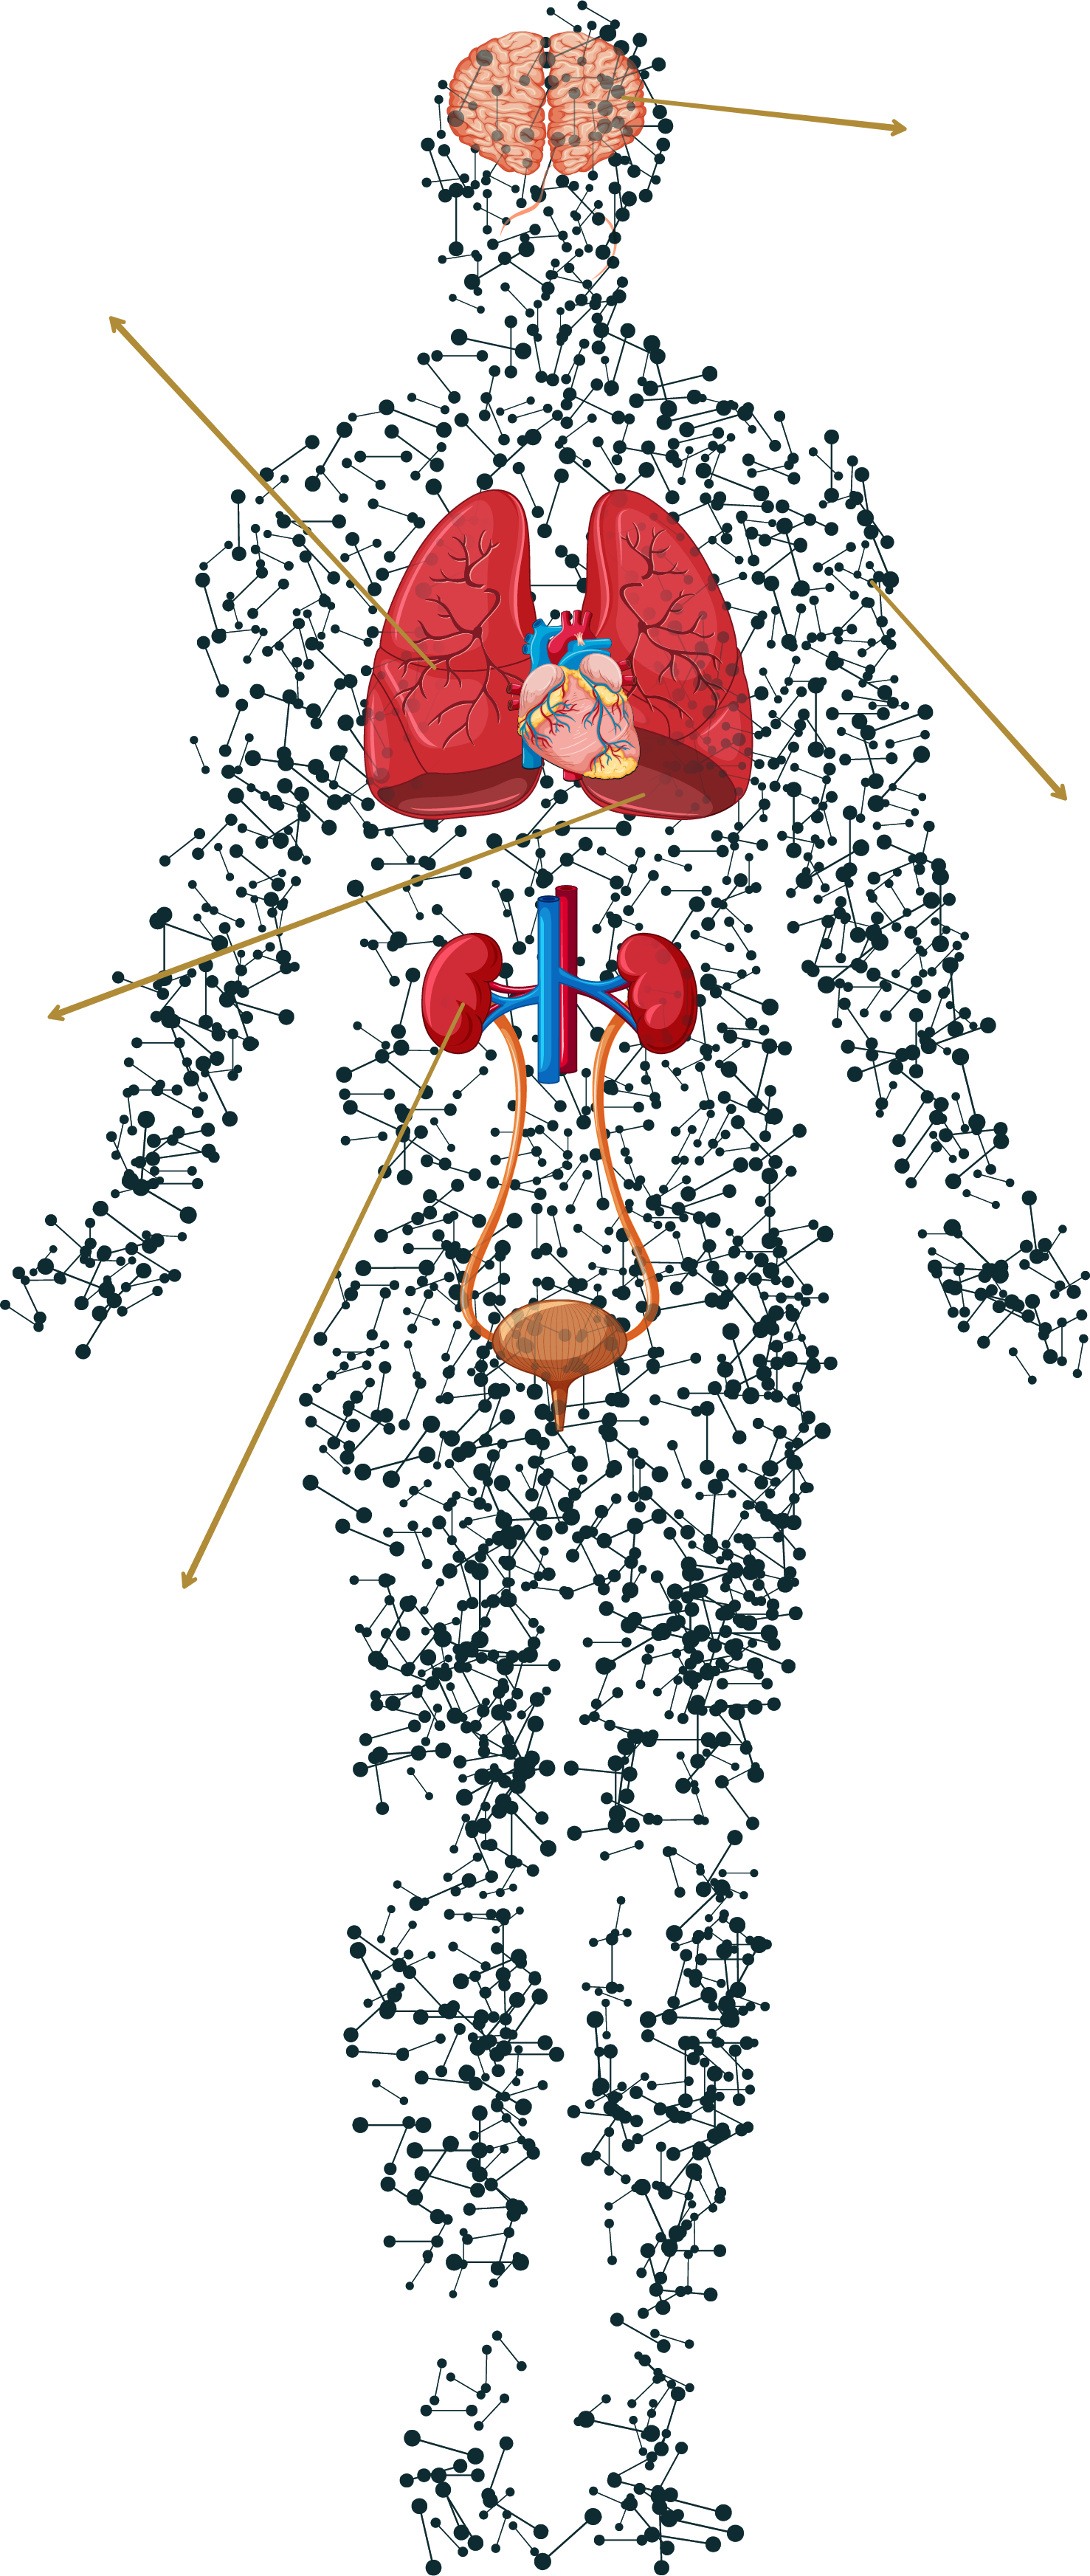

When present in excess, ROS can damage cells by oxidizing essential biomolecules like proteins, lipids, and nuclei Cellular senescence or even Cell Death.

This may lead to various cellular dysfunction, including DNA damage, lipid peroxidation, and protein damage, ultimately contributing to cell death and to various diseases including aging and cancer.

ROS from Ozone and PM2.5 cause inflammation in Lung tissue leading to:

Pollutant particles in the air damage blood vessels and promote clotting leading to:

EDCs like PFAs, BPA and pesticides disrupt the signalling mechanisms leading to:

ROS cross the BBB contributing to loss of higher order thinking skills, and leading to:

PAHs and PCBs damage the layer of the skin leading to:

ROS from Ozone and PM2.5 cause inflammation in lung tissue leading to:

ROS cross the BBB contributing to loss of higher order thinking skills, and leading to:

EDCs like PFAs, BPA and pestiicdes disrupt the signalling mechanisms leading to:

Pollutant particles in the air damage bloodvessels and promote clotting leading to:

PAHs and PCBs damage the layer of the skin leading to: